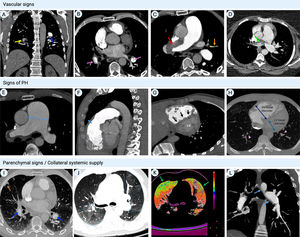

CTEPH should also be suspected at the time of acute PE when CTPA shows findings suggestive of chronic fibrothrombotic deposits – bands, webs, arterial narrowing or retraction, and/or dilated bronchial arteries (Figure 5) – or when the echocardiogram depicts an estimated PASP >60 mmHg and/or features of RV dysfunction and hypertrophy.14 In asymptomatic patients with risk factors (Figure 1) or a high CTEPH prediction score (Table 1),20 diagnostic assessment should also be considered.2 A proposed diagnostic algorithm is shown in Figure 6. Initial assessment of patients with suspected CTEPH should include a transthoracic echocardiogram to determine the probability of PH (Table 2) and a V/Q scan to look for mismatch perfusion defects.2 In general, especially considering that CTPA performed by chest radiologists is not widely accessible, a V/Q scan remains the gold standard exam for exclusion of CTEPD without PH at rest, due to its high sensitivity (96.2–97.4%) and negative predictive value of almost 100%47,48 (Figure 7). Other perfusion techniques, such as dual-energy CT scan or magnetic resonance perfusion, may be superior to a V/Q scan (Figure 8). However, these are more technically challenging and expensive, have limited availability, and lack multicenter validation.3

Computed tomography pulmonary angiography findings in chronic thromboembolic pulmonary hypertension. (A) Coronal image showing fibrothrombotic retraction with partial obstruction (yellow arrow) and eccentrically located thrombus with a broad base forming obtuse angles with the vessel wall, due to incomplete thrombus resolution (blue arrow); (B) axial image with intravascular webs (purple arrows); (C) axial image with total left PA occlusion (red arrow) and segmental arterial retraction (orange arrow); (D) calcifications within fibrothrombotic deposits in the right PA, illustrating the chronic component of the disease (green arrows); (E) axial image depicting main PA dilatation (double-headed arrow); (F) sagittal image showing RV outflow tract hypertrophy (double-headed arrow); (G) cardiac short-axis image with flattening of the interventricular septum (black arrows) and D-shaped left ventricle; (H) axial image showing segmental artery-to-bronchus diameter ratio of >1:1 (arrowheads), flattening of the interventricular septum, RV hypertrophy and RV/LV diameter ratio >1 (double-headed arrow); (I) peripheral nodular opacity (brown arrow) in the right upper lobe secondary to previous pulmonary infarction along with intra-arterial fibrothrombotic deposits (blue arrows); (J) axial image showing sharply demarcated segmental and subsegmental areas of hypo- and hyperattenuation (dotted lines); (K) (same patient as in panel J) color maps showing the distribution of perfusion: spectrum from green to red indicates increasing perfusion (hypoperfusion indicated by green areas); (L) sagittal image with bronchial artery hypertrophy (blue arrows). LV: left ventricular; PA: pulmonary artery; RV: right ventricular.

CTPA is currently used to confirm the presence of CTEPD and to assess operability, providing detailed information on endovascular thrombi, vascular wall thickness, and the presence of bands/webs, stenosis and bronchial artery collateral circulation2,48 (Figure 5). CTPA also enables differential diagnosis of PH, as it can detect underlying parenchymal lung or mediastinal disease and other causes of vascular occlusion (PA sarcoma, arteritis, in-situ thrombosis or congenital anomalies).48 Technological advances have improved the diagnostic performance of this exam. A recent meta-analysis of 10 studies demonstrated high sensitivity (98%) and specificity (99%) for CTPA in the detection of CTEPD on a vessel-based analysis.49 However, these exams were assessed by expert chest radiologists, and CTPA still has lower sensitivity for detecting CTEPD in segmental and subsegmental vessels.48 Therefore, a negative CTPA does not exclude CTEPD, and digital subtraction angiography may be necessary to fully assess treatment options.2 Novel techniques such as cone-beam CT and area-detector CT are being increasingly used, as they provide better visualization of segmental and subsegmental disease and are useful for guidance of BPA therapy,50–52 but they still require validation in prospective trials.2